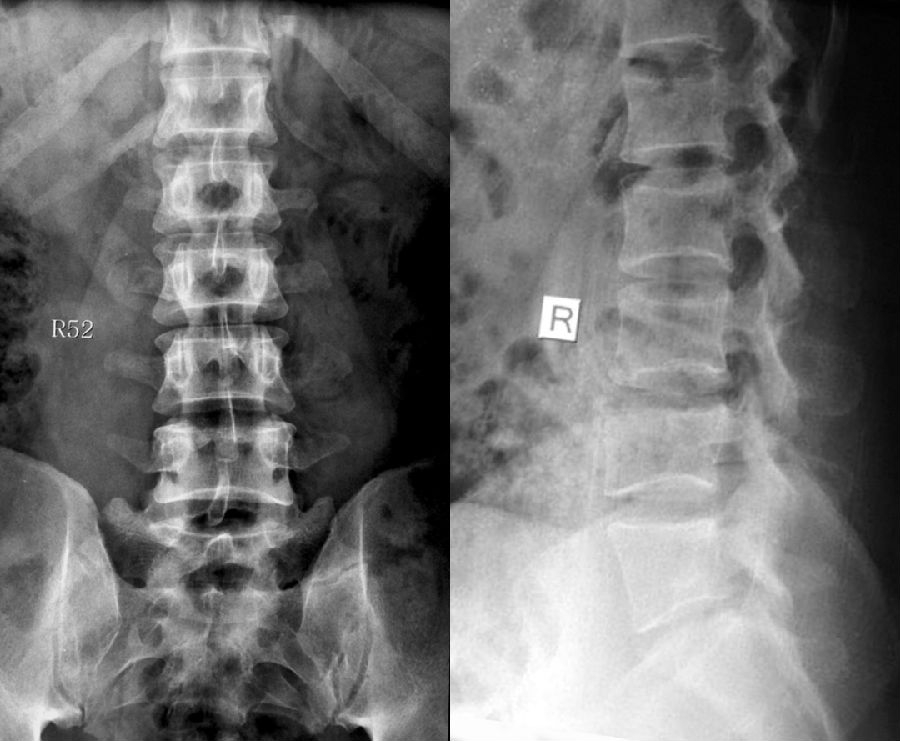

Ia型(单侧)和Ib型(双侧):横突肥大宽度超过19mm

IIa型(单侧)和IIb型(双侧):横突与骶骨相接触形成假关节

IIIa型(单侧)和IIIb型(双侧),横突与骶骨发生骨性融合

IV型:一侧横突与骶骨形成假关节另一侧形成骨性融合

L5右侧横突肥大,为Ⅰa型

L5双侧横突肥大,为Ⅰb型

L5左侧横突肥大,假关节形成,为Ⅱa型

L5双侧横突肥大,假关节形成,为Ⅱb型

L5右侧横突肥大与骶骨发生骨性融合,为Ⅲa型

L5双侧横突与骶骨骨性融合,为Ⅲb型

IV型即混合型:L5双侧横突肥大,一侧与骶骨相接触为Ⅱ型表现,另一侧与骶骨形成骨性融合为Ⅲ型